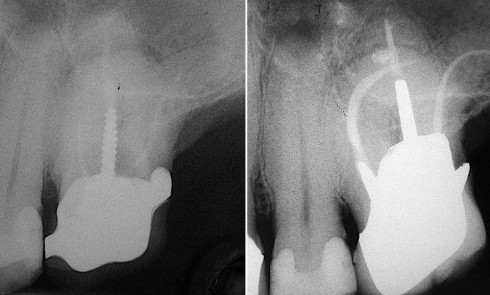

Article réservé à nos abonnés Situations endodontiques complexes : jusqu’où aller en pratique généraliste ?

Une méta-analyse publiée en 2021 rapporte qu’un adulte sur deux dans le monde présente au moins une dent avec une...